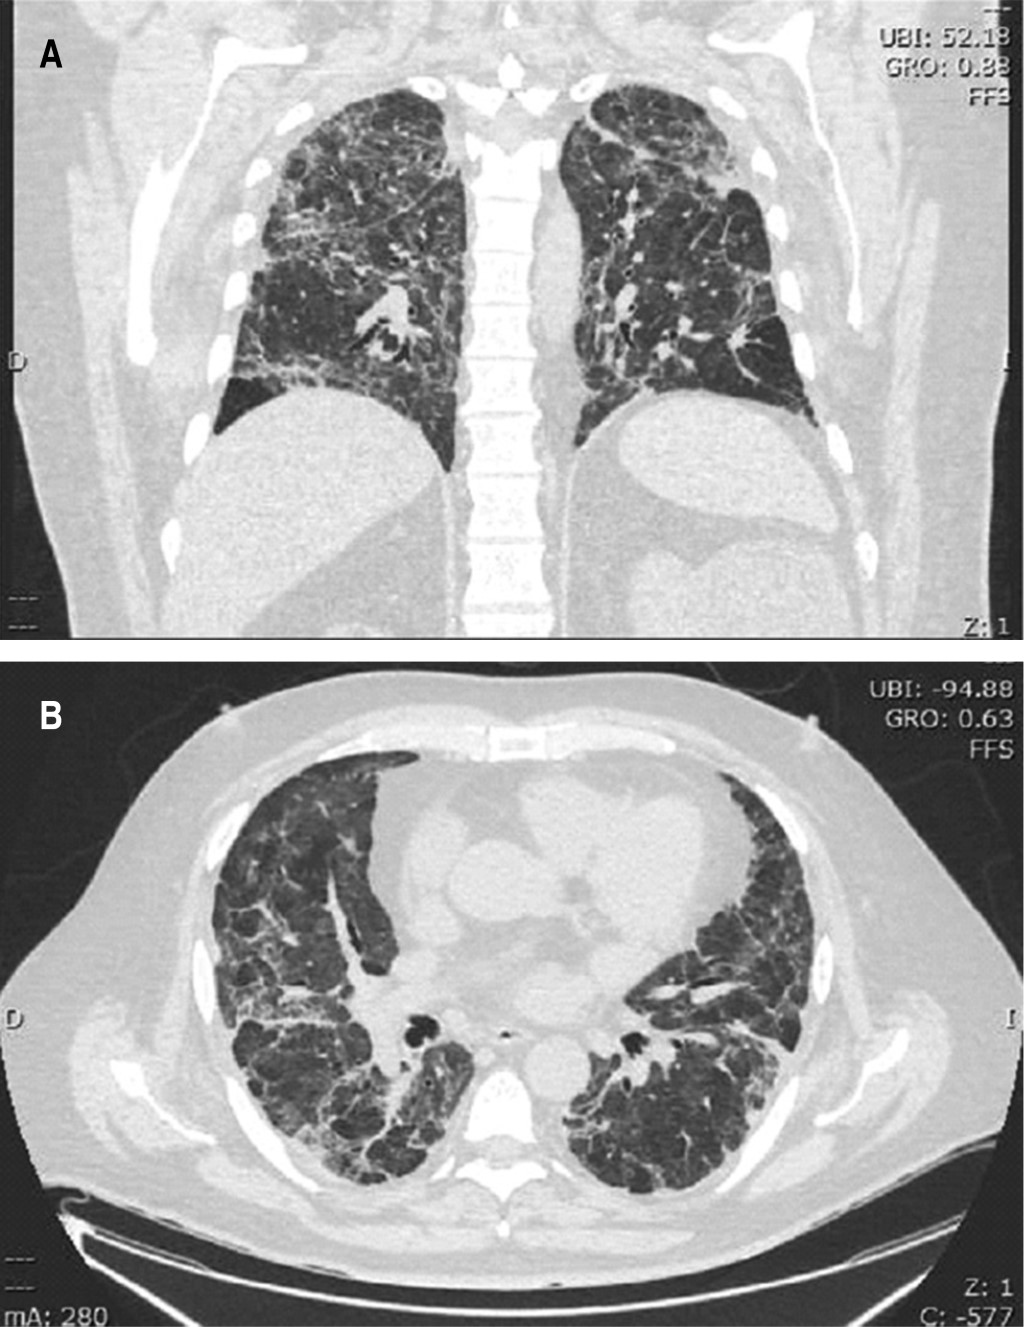

Acinetobacter baumannii with extended resistance in a post-COVID-19 patient

The pandemic caused by the SARS-CoV-2 coronavirus has generated a global problem and disrupted life in different areas, mainly in coexistence, economy and health. Due to the characteristics of the disease caused by this virus, the superinfections, similarities in the clinical manifestations, the indiscriminate use of antibiotics and the ignorance of this new pathogen, has generated negative consequences in the treatment. In addition to the great problem generated by antimicrobial resistance, which keeps all health systems on alert. The inadequate management of this pandemic and its treatments will undoubtedly contribute to increasing bacterial resistance, resulting in the appearance of strains that present multi-resistance and pan-resistance in bacteria, but undoubtedly also in parasitic viruses and fungi. The case of a 54-year-old male patient with various comorbidities and multithreaded who suffered from COVID-19 infection and, after his recovery, acquired additional nosocomial urinary infection, during his hospitalization, due to multidrug-resistant Acinetobacter baumannii that required combination and antimicrobial synergy is presented. It highlights the importance of doctor-laboratory communication to better deal with the increasing antimicrobial resistance.

Figure 1